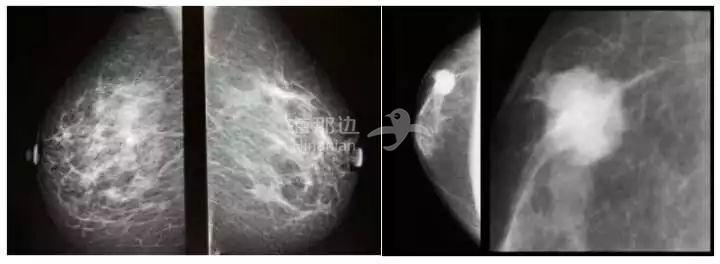

可以得到如下图的影像结果:

在上图中,我们可以看到乳房组织中有高密度肿块或者毛刺样结构,这些就是乳房内的肿瘤,根据肿瘤性质、阶段和分布,有团块样的,也有分散的。